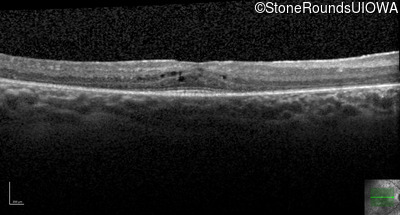

Optical Coherence Tomography - Left - 20/32 +1

Exemplar / OCT Stack

OCT Stack